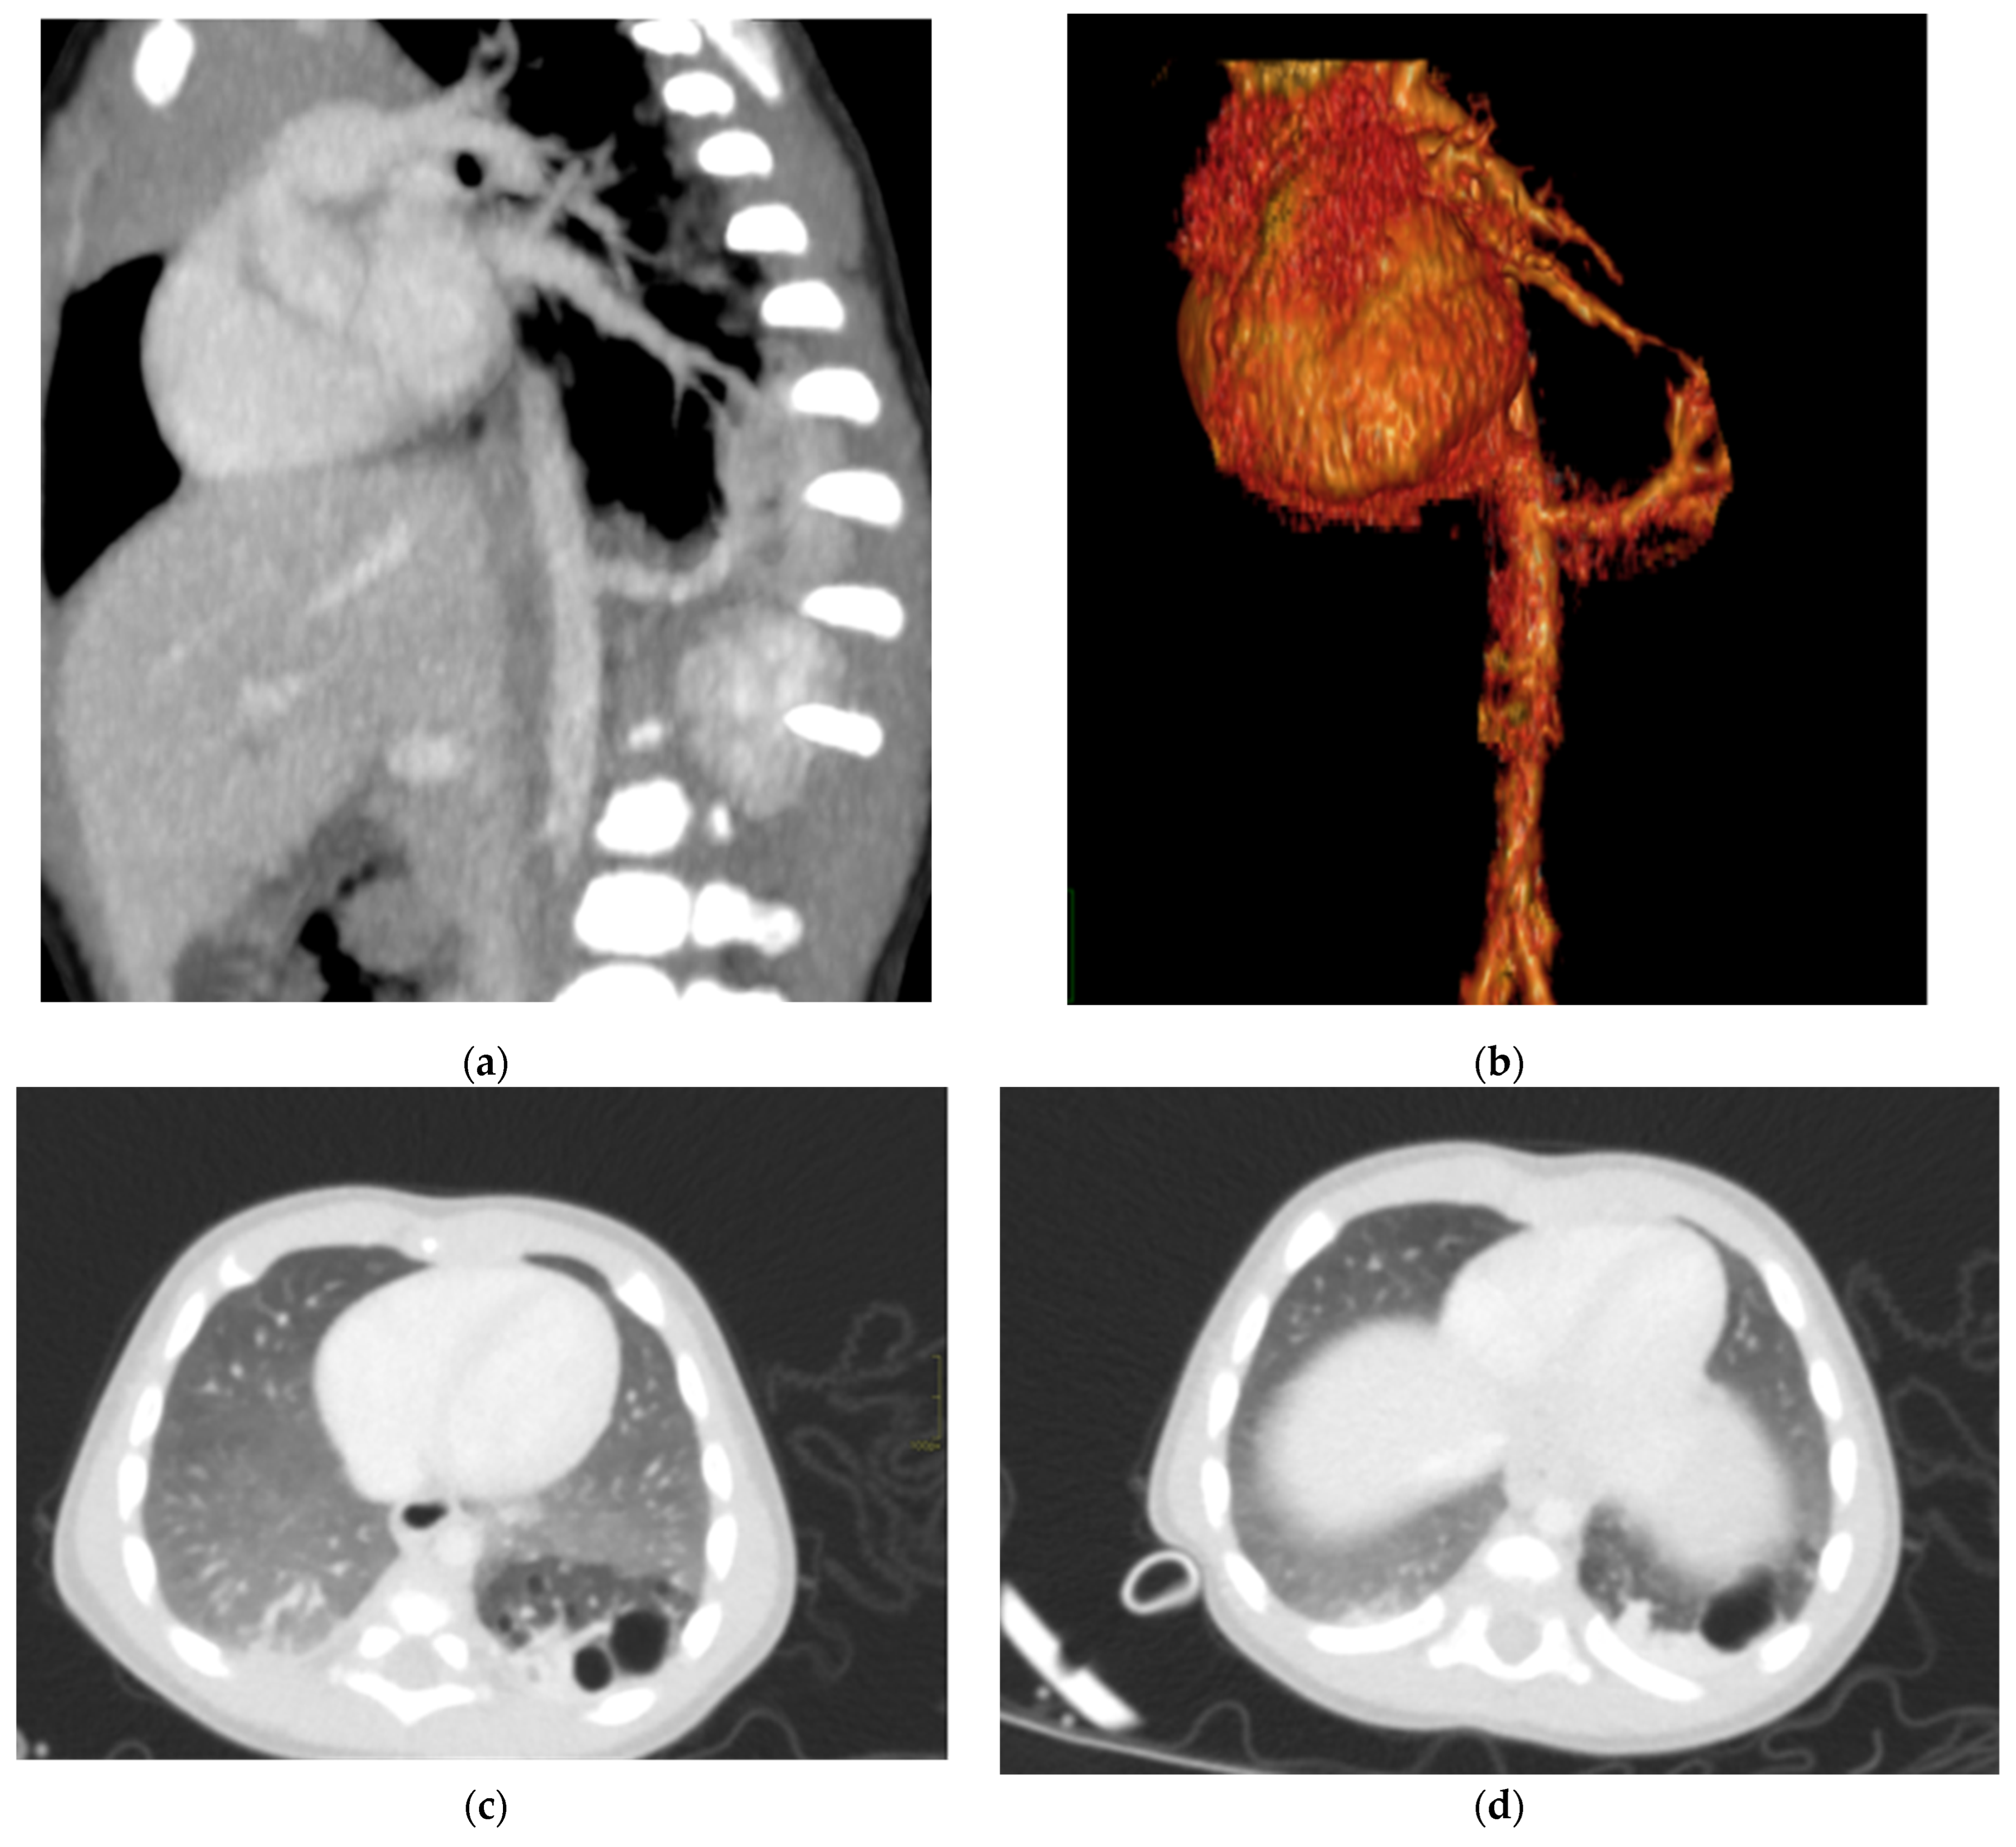

Figure 6. Hybrid congenital malformation consisting of lung seizure and CCAM. CECT MPR reconstruction (a), VR (b), and axial (c,d) images show the presence of a lobulated-margin formation located in the lower lobe of the left lung, which is consists of multiple cystic formations (diameters ranging between a few millimeters and 1.5 cm) and a consolidation zone corresponding the costodiaframmatic recess, which is supplied by a voluminous arterial branch originating from the left lateral wall of the aorta in the thoraco-thoracic passage.